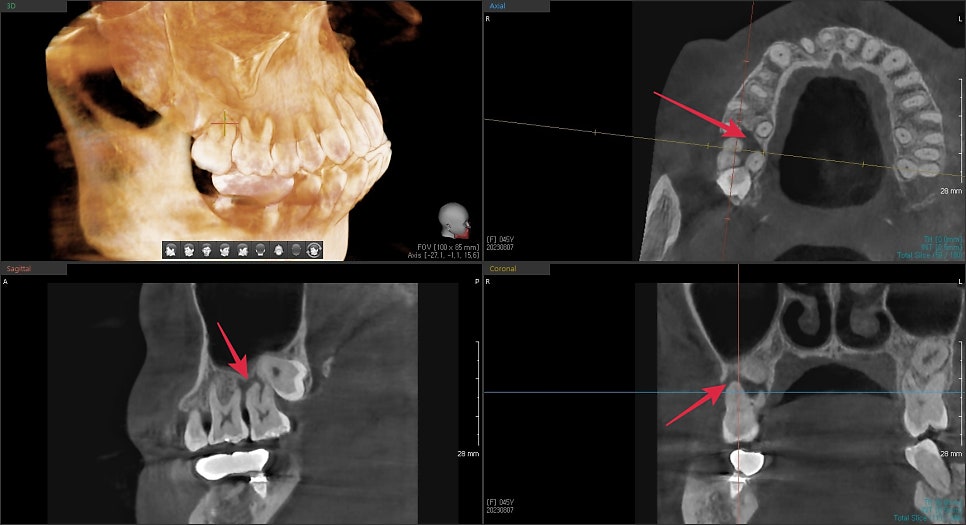

해당 부위의 여러 단면을 촬영한 3D CT입니다.

화살표 표시된 부분이 하얗게 뼈로 채워져있어야 할 공간이

염증에 의해 뿌리 주변이 모두 녹아 뿌리가 외부 자극에 그대로 노출이 되어있었습니다.

이미 뿌리 밑단까지 녹아있었기에 해당 치아와 그 옆의 사랑니까지 발치가 필요해 보였습니다.

또한, 그 옆의 치아도 염증이 퍼져 치주 질환에 이환되어 뿌리의 절반이 노출되었습니다.

이 치아 또한 장기적으로 문제가 생길 소지가 높지만 일단 발치 후 증상을 체크하고

시간이 지난 후에 주변이 재생이 안될 경우 발치 가능성을 고지하고 지켜보았습니다.